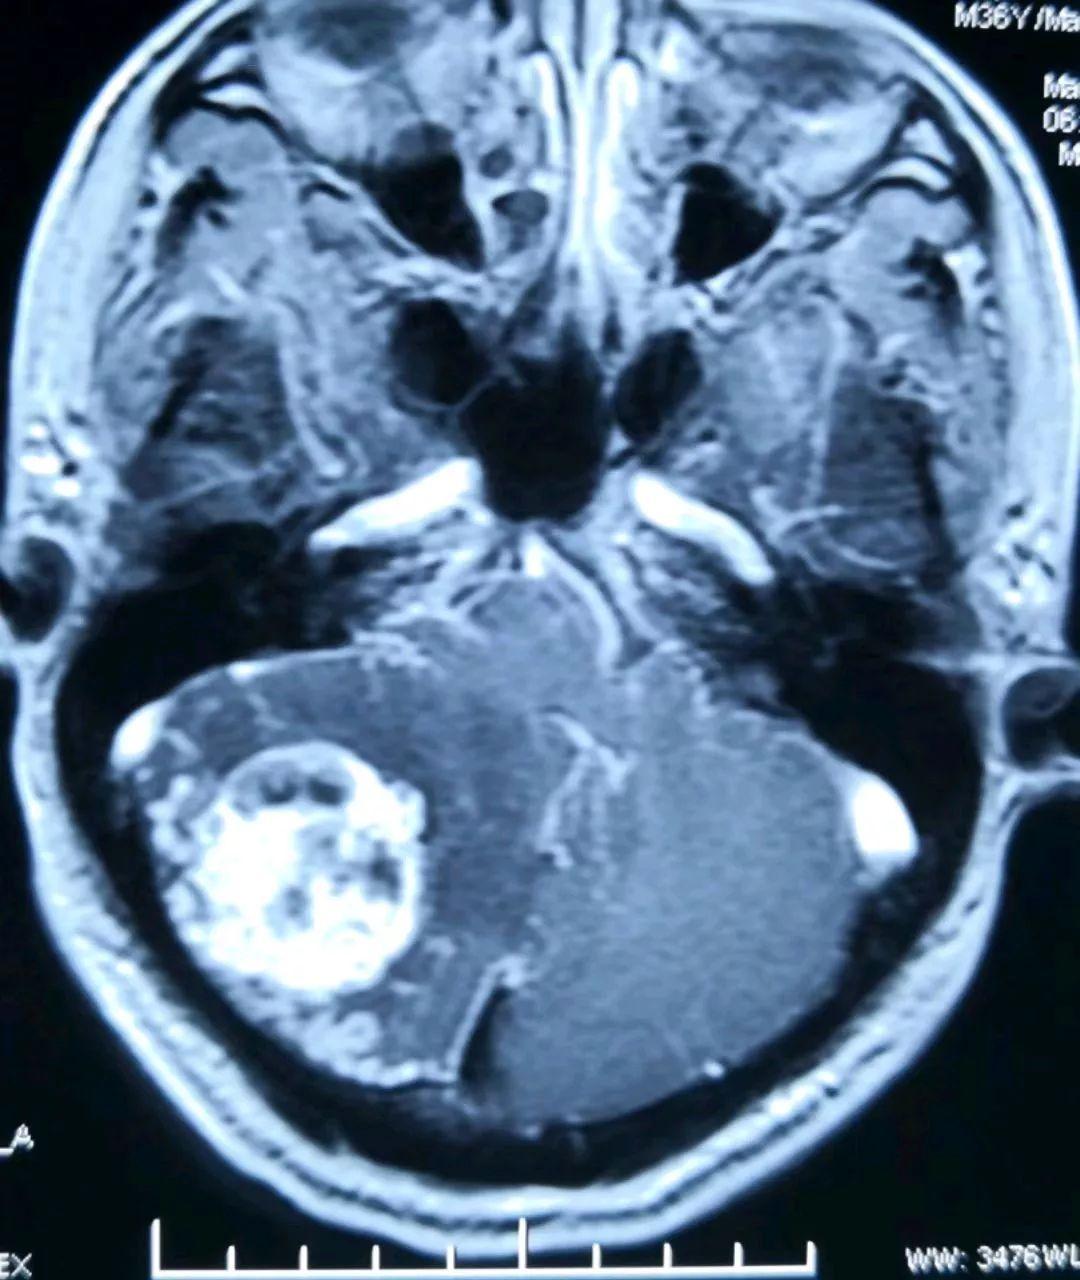

术前的磁共振片子提示右侧小脑半球的实质性血管母细胞瘤,增强显著(提示血供丰富)

另一位置的增强磁共振提示肿瘤长向小脑深部,靠近脑干组织(人的生命中枢)